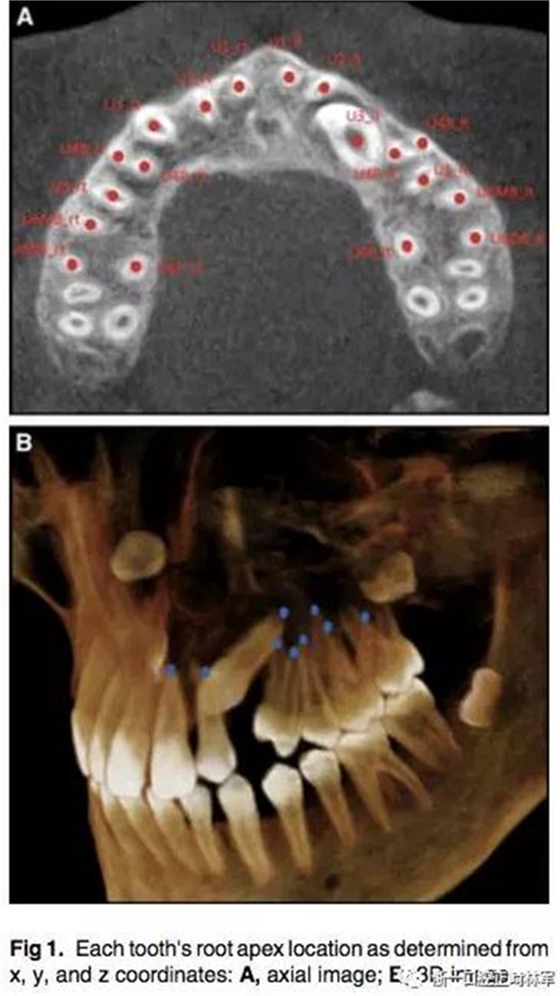

通過CBCT來確定尖牙牙根的具體位置,以x,y,z三維坐標(biāo)表示。我們定義在面中線上,鼻根點(diǎn)作為鼻額縫在額骨上的最前點(diǎn),CBCT掃描儀與腭平面水平。我們用3個標(biāo)志點(diǎn)(前鼻棘點(diǎn),兩側(cè)腭大孔的中心點(diǎn))來定位腭平面,將鼻根點(diǎn)坐標(biāo)定為(0,0,0),以此確定上頜牙齒根尖點(diǎn)的x,y,z的坐標(biāo)。由于上頜前磨牙和磨牙有2-3個牙根,因此將多個牙根的中心點(diǎn)作為根尖點(diǎn)。見Fig1.